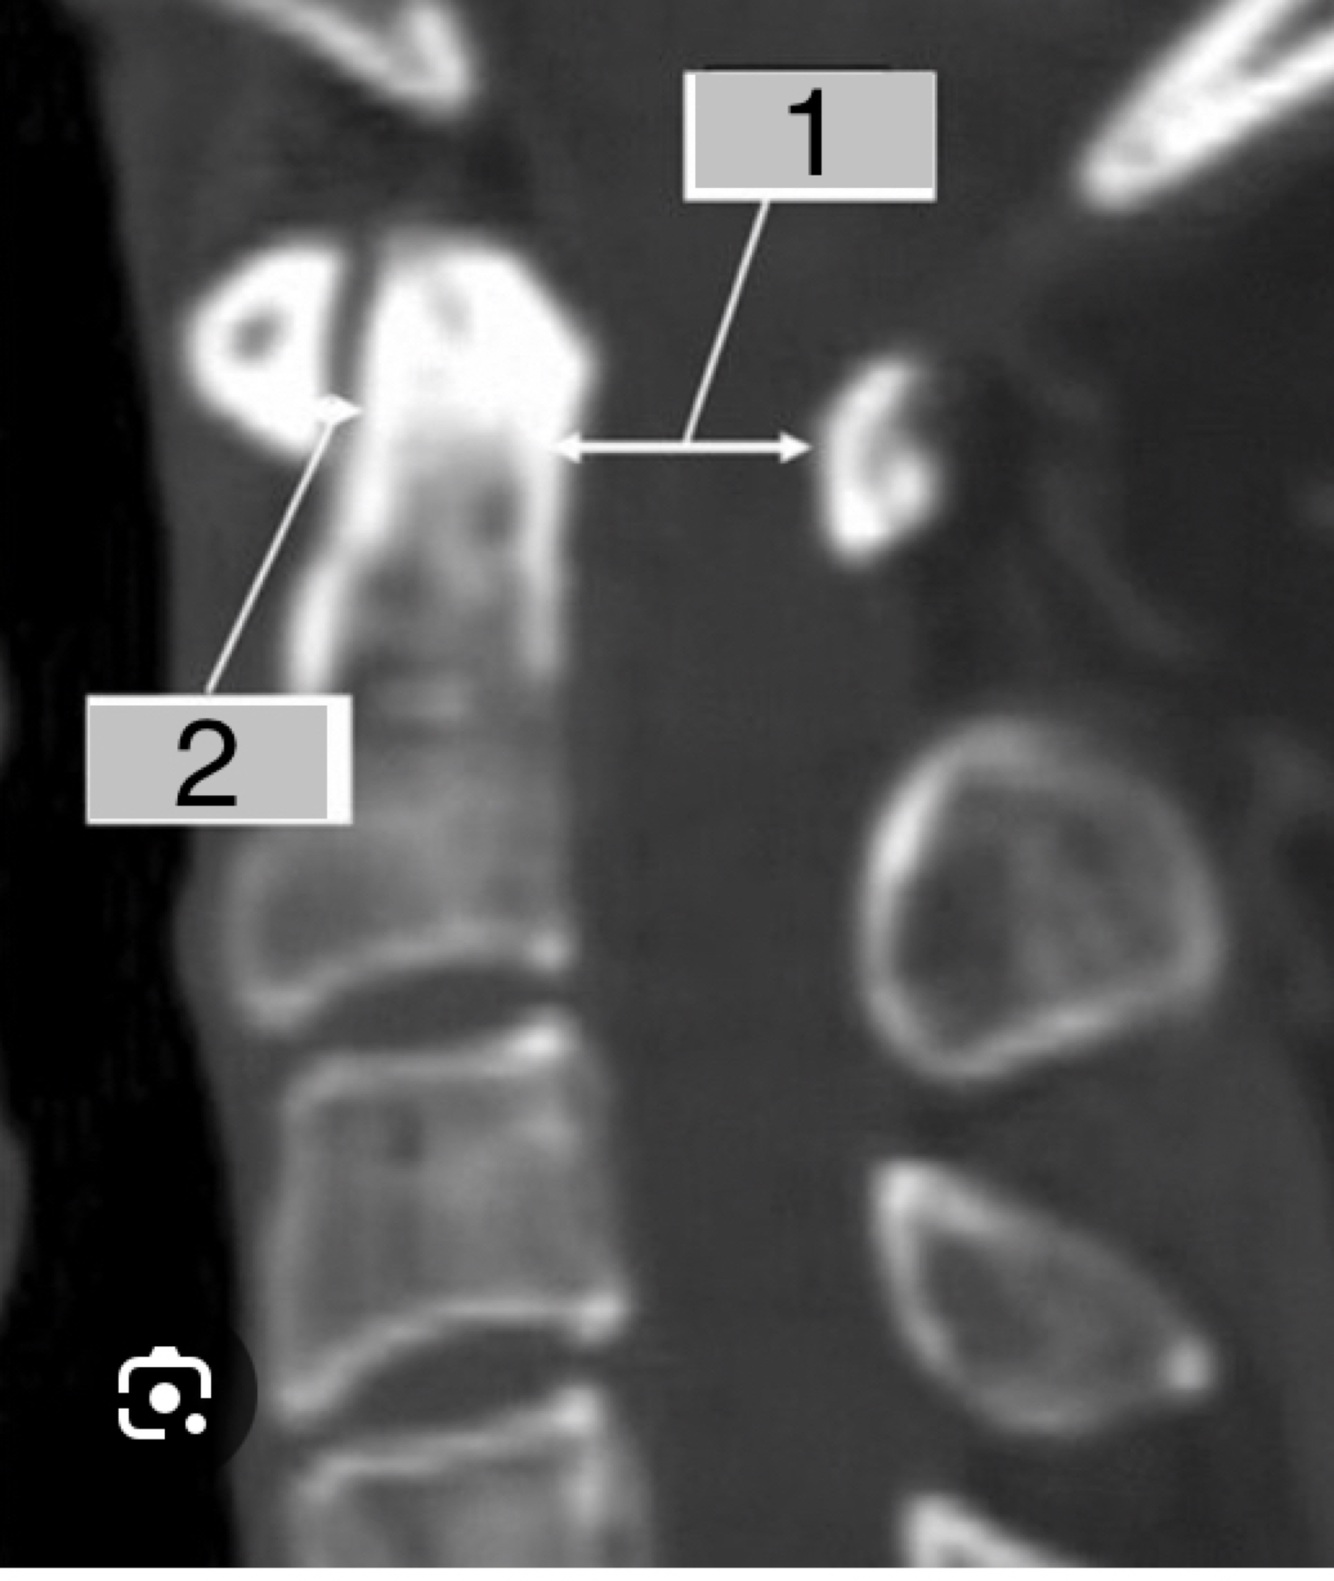

Lesão Ligamento Transverso: quais valores definem lesão?

A

2- Intervalo Atlanto Odontoide Anterior: normal <5mm criança ou <3mm adulto

Lesão Lig Transverso: 3-5mm

Lesão Lig Transverso+Alar: >5mm